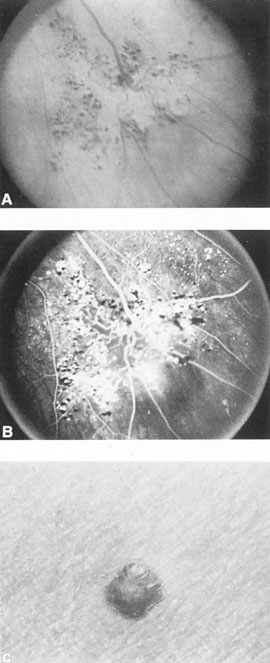

Fig. 7. Supratentorial arteriovenous malformation in a 28-year-old woman with a history of focal motor seizures for many years and a recent subarachnoid hemorrhage. A: Lateral projection carotid arteriogram demonstrating a huge deep hemispheral arteriovenous malformation. B: Frontal projection. C: Fundus photograph showing anomalous tortuous vasculature in each eye. No retinal arteriovenous shunt was detectable.

From 85% to 90% of AVMs are in the supratentorial compartment and are supplied primarily by the carotid circulation (Figs. 7 and 8). The remainder are supplied by the vertebrobasilar system. The approximate frequency of location is as follows: frontal, 22%; temporal, 18%; parietal, 27%; occipital, 5%; and deep intraventricular or paraventricular, 18%. The intracerebral site of the malformation does not necessarily indicate that there will be signs referable to that area simply from the mass effect of the malformation. Clinical features primarily result from subarachnoid hemorrhage or intraparenchymal hemorrhage with hematoma formation.

Fig. 9. Carotid arteriogram of an occipital lobe arteriovenous malformation (AVM). Lateral (A) and frontal (B) projections demonstrating a small occipital AVM (arrow). The patient was a 23-year-old woman who presented with severe apoplectic unilateral headache, total left homonymous hemianopia, and mild nuchal rigidity. Despite xanthochromic cerebrospinal fluid, she was initially diagnosed elsewhere as having migraine. An AVM was successfully resected, and a small occipital lobe hematoma was removed.

Of particular interest are those AVMs that involve the occipital lobe (Fig. 9). The clinical differentiation of migraine from a cerebral AVM was previously regarded as difficult because the clinical features of occipital lobe AVMs include visual phenomena or headaches. However, in most cases the clinical distinction is possible. In 26 cases with occipital AVM, two distinct syndromes were defined in 18 patients: occipital epilepsy and occipital apoplexy.73 Focal seizures with occipital malformations consist of elementary visual sensations similar to the phenomena evoked by direct cortical stimulations. When seizure activity occurs in the striate cortex (area 17), the patient usually reports sensations of moving lights in the right or left homonymous fields. The sensations are poorly formed, episodic, usually brief, sometimes colored, and unassociated with the angular, scintillating figures so characteristic of migrainous cortical phenomena. Epileptic discharges from areas 18 and 19 cause photopsias that are unlikely to remain stationary and to flicker rapidly. The epileptic photopsias usually last only seconds; occasionally they last for a few minutes before the onset of a generalized seizure. In other instances only the brief visual episodes occur without spreading to produce a generalized seizure. Momentary dimming or blindness in one or both homonymous fields may be experienced with seizure activity in the occipital areas.